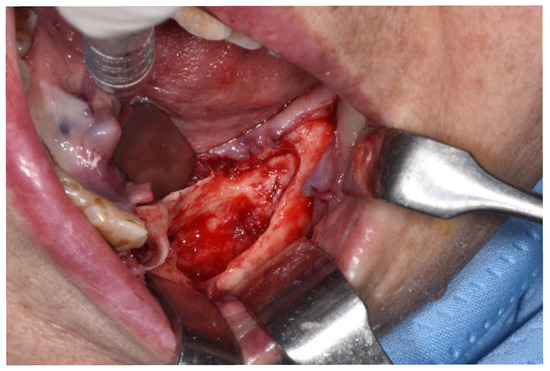

Figure 5.

Intraoperative aspect. Necrotic bone segment was observed macroscopically and cut, dividing it into three parts: a transitional zone (segment located in the mesial third of the sequestrum), totally necrotic tissue (the middle part of the segment) and healthy adjacent tissue (the distal area of the segment). The arrow schematically indicates the portion used in this case.